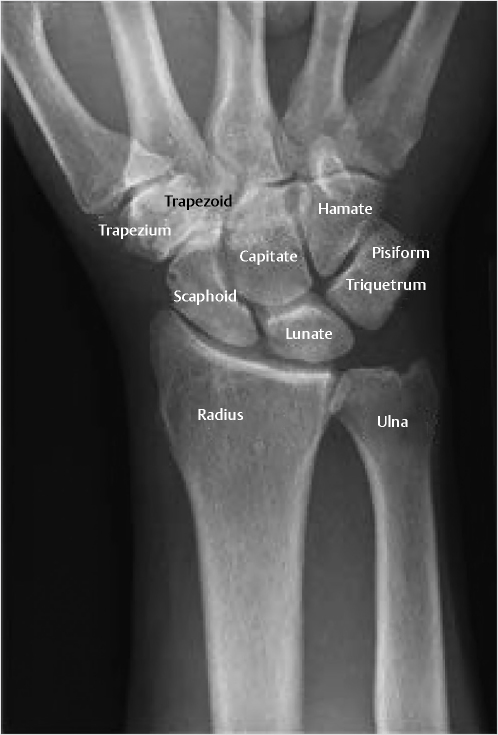

The hand and wrist has a total of 27 bones. The wrist is made of the distal ends of the radius and ulna, the eight carpal bones, and the proximal ends of the five metacarpals. The carpal bones consist of two rows of four bones each. The proximal row includes radial to ulnar, the scaphoid, lunate, triquetrum, and pisiform (Fig. 2‑1). The distal row includes radial to ulnar, trapezium, trapezoid, capitate, and hamate. The proximal carpal row is considered intercalated because no tendons insert on them and their motion depends on their surrounding articulations. The distal row is connected to each other by short intercarpal ligaments, resulting in negligible motion between them. The extrinsic carpal ligaments connect the distal radius and ulna to the carpal bones. The intrinsic ligaments have their origins and insertions within the carpal bones. When a surgeon wants to enter the wrist joint, he makes a dorsal “ligament sparing” incision, which looks like a radially based “V.” This incision splits the dorsal radiotriquetral (radiocarpal) ligament and the dorsal intercarpal ligament. These ligaments are felt to play an important role in stabilizing the proximal carpal row. Palpable landmarks are the sulcus between the scaphoid and trapezoid, the dorsal tubercle of the triquetrum, and the midpoint between Lister’s tubercle and the dorsal rim of the sigmoid notch (Fig. 2‑2). 1